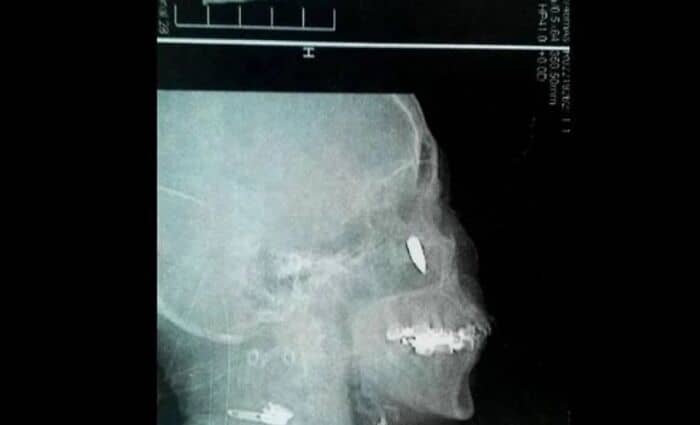

#53

A Chinese woman with chronic rhinitis was suffering from headaches and breathing issues. An exploratory x-ray revealed a bullet lodged in her head by her nostril.

She then remembered back 48 years ago to when she was 14, and walking along a path. The woman felt a stinging pain in her temple and started to bleed.

She thought she’d been hit by a pebble; so her family cleaned her up and threw a bandage on it. Apparently she was shot.